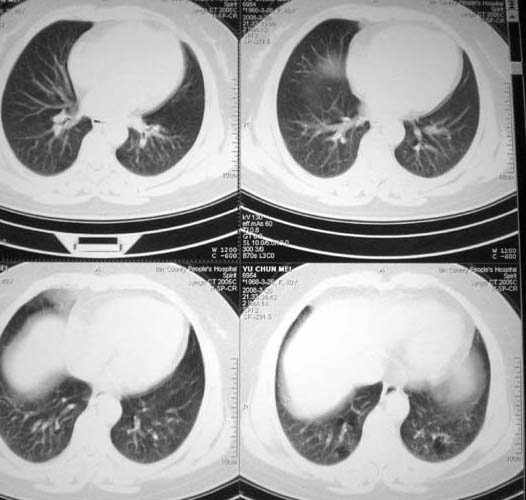

以下是引用doc张在2008-3-27 9:20:00的发言:[br]可见小叶中心型肺气肿.

以下是引用有风的日子在2008-3-27 16:59:00的发言:[br]片子上的信息与提供资料有矛盾点:到底是40岁还是56岁?[br]双下肺野可见散在、大小不等的无壁高透过影,支持小叶中心性肺气肿诊断[br]女同志有80%的症状与情绪有关,有能全靠疾病解释